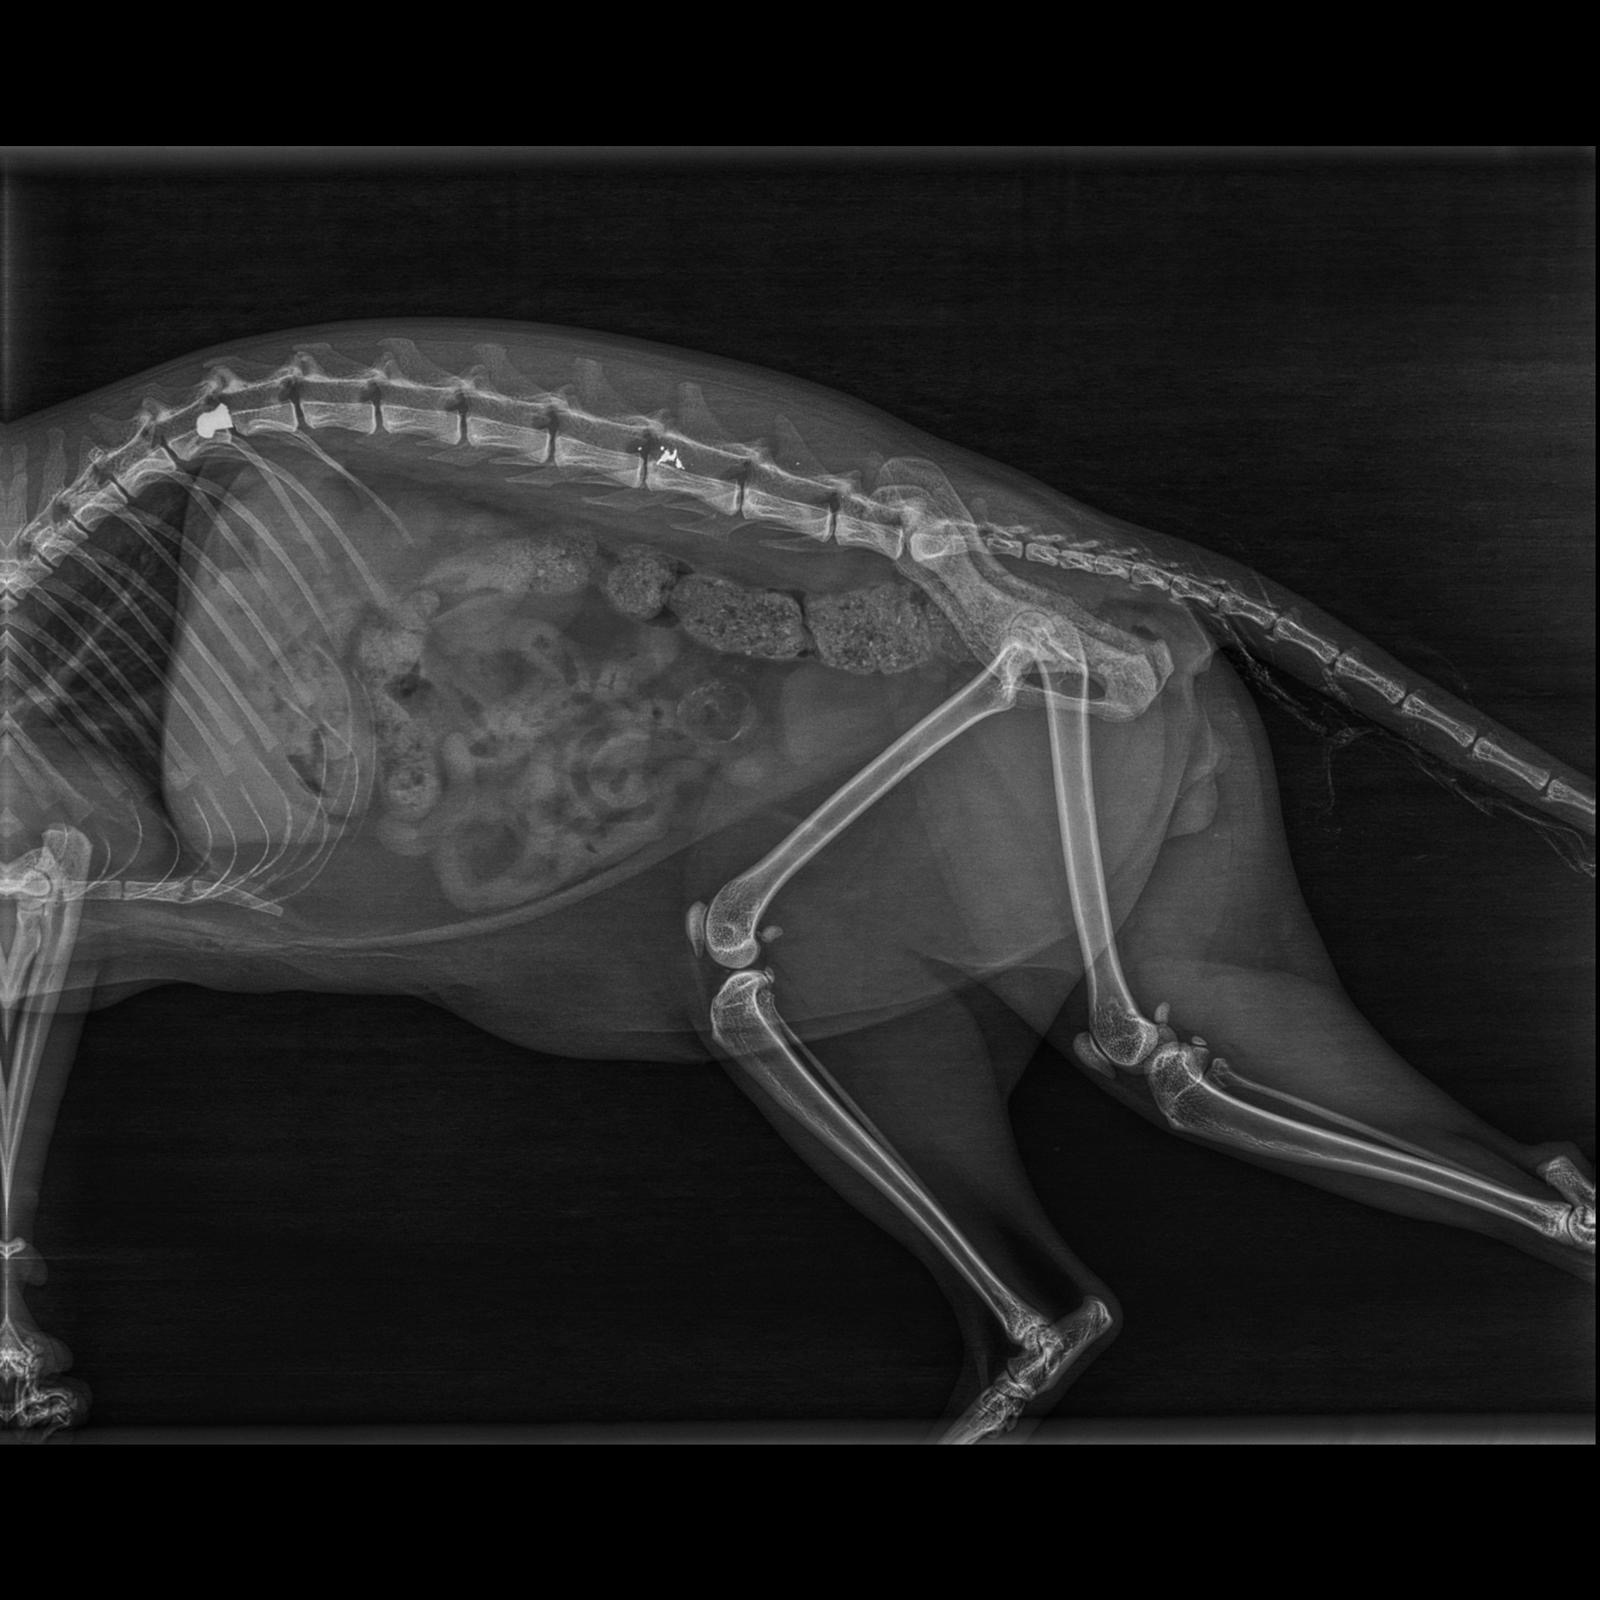

Hace una semana, alguien del vecindario le disparó con una escopeta de perdigones en la puerta de casa. No es la primera vez que ocurre. Esta vez, la herida fue tan grave que Elmo perdió la movilidad de las patas traseras y, tras varias pruebas, ha tenido que ser operado de urgencia para tratar una infección en la médula, donde habían llegado restos de metralla.

Las radiografías muestran varios perdigones antiguos y nuevos. Durante los primeros días apenas podía moverse, no controlaba sus necesidades y tenía la mirada perdida. Poco a poco se está recuperando, pero el proceso es largo y los gastos veterinarios ya superan los 3.500 €.